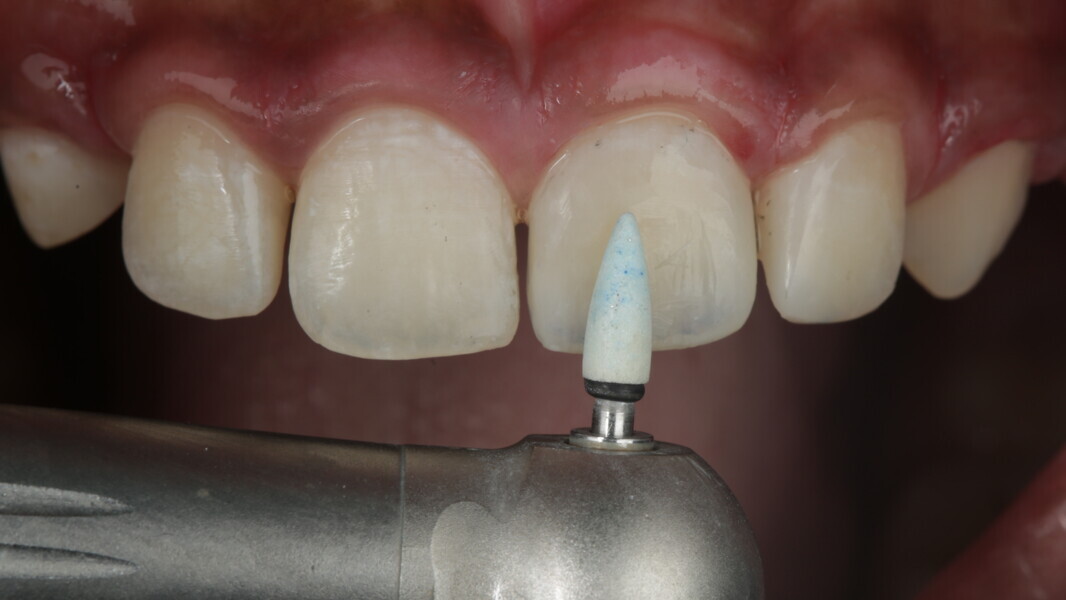

Fig 31-41: Polishing protocol and post-op

The article demonstrates how using the right protocols and armamentarium for composite materials can give life-like results in a short time in a minimally invasive way. No single layering technique can ensure a 100% success rate. Regardless of the technique, establishing good secondary and tertiary anatomy and thorough polishing are the key steps that make a restoration look more natural. Composite is the perfect material for allowing correction of mistakes or improvement.